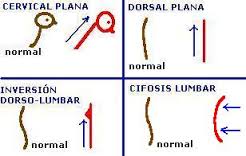

567 × 198 - gimolimpo.com

{"id":"DvwZdj2ArqSFrM:","isu":"gimolimpo.com","itg":1,"ity":"jpg","oh":198,"ou":"http://www.gimolimpo.com/Paginas/esqueleto%20lateral_archivos/l9.jpg","ow":567,"pt":"esqueleto

567 × 198 - gimolimpo.com

{"id":"XAtAelJvo4XsmM:","isu":"gimolimpo.com","itg":1,"ity":"jpg","oh":198,"ou":"http://www.gimolimpo.com/Paginas/esqueleto%20lateral_archivos/l10.jpg","ow":567,"pt":"esqueleto

567 × 198 - gimolimpo.com

{"id":"5HhauqhjHVAK8M:","isu":"gimolimpo.com","itg":1,"ity":"jpg","oh":198,"ou":"http://www.gimolimpo.com/Paginas/esqueleto%20lateral_archivos/l12.jpg","ow":567,"pt":"esqueleto

567 × 235 - gimolimpo.com

{"cb":6,"cl":9,"cr":21,"id":"Ey_6BxTow7E_cM:","isu":"gimolimpo.com","itg":1,"ity":"jpg","oh":235,"ou":"http://www.gimolimpo.com/Paginas/esqueleto%20lateral_archivos/l13.jpg","ow":567,"pt":"esqueleto

lateral","rid":"hh0jD0oz9bYblM","rmt":0,"rt":0,"ru":"http://www.gimolimpo.com/Paginas/esqueleto%20lateral.htm","s":"Volver.","sc":1,"th":144,"tu":"https://encrypted-tbn0.gstatic.com/images?q\u003dtbn:ANd9GcRnpqkNbUnpImzKHrwhCsrw5GM151AQFUq55_5A9axK4XgRamyb","tw":349}